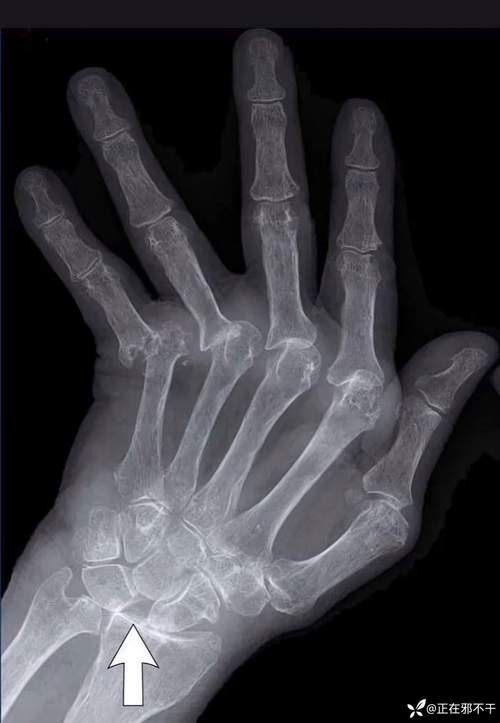

骨侵蚀

- 表现:这是RA的特征性、具有诊断意义的X线征象,骨质边缘出现边界清晰的虫蚀状、小囊状的骨质缺损区。

- 典型部位:

- 手部:掌指关节的尺侧(小指一侧)和近端指间关节的桡侧(拇指一侧)是最经典的部位。

- 腕部:尺骨茎突的侵蚀、舟状骨的破坏、以及桡尺远侧关节的受累非常常见。

- 足部:第5跖骨头的侵蚀是另一个典型表现。

- 特点:骨侵蚀的边缘通常没有骨硬化(与骨关节炎不同),因为它是一种活跃的、进行性的破坏过程。